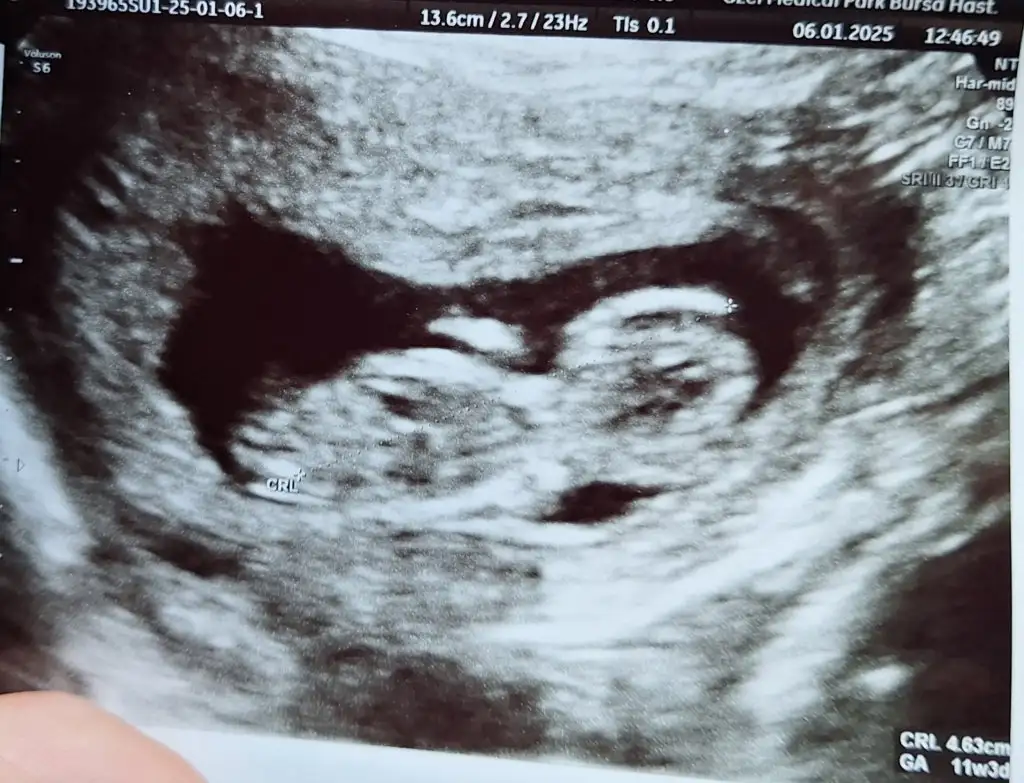

Hanımlar selam 13+2 den selam kontrolden çıktım şimdi.

Cinsiyet tahmini olan var mı? 🤣🤣🤭🤭🤭🤭